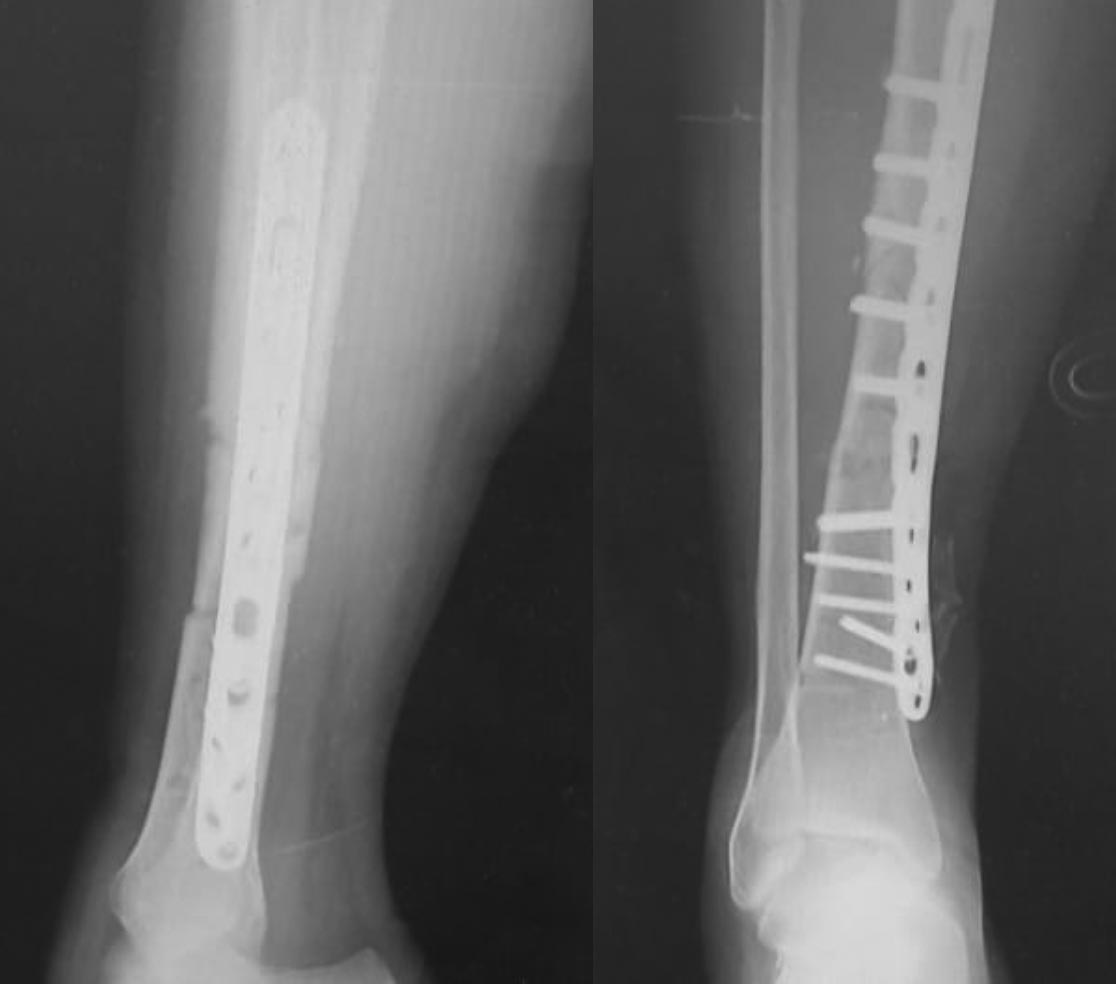

Посев из раны отрицательный.Посев крови на стерильность в работе. Снимки.